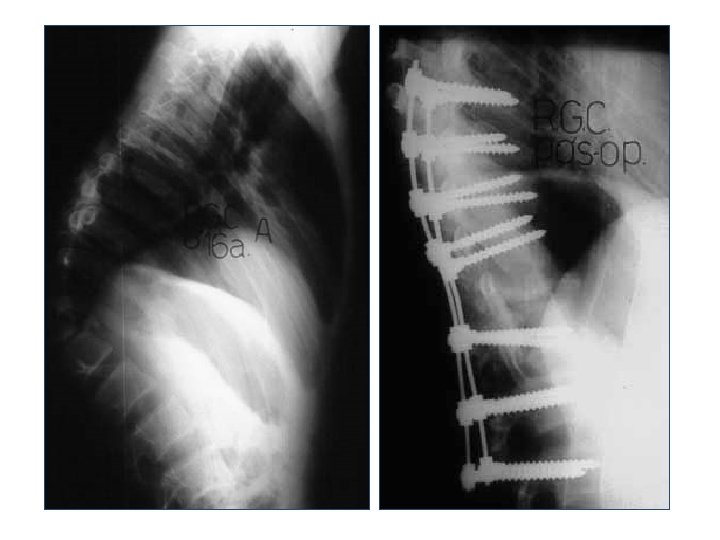

Exames complementares • Radiografia • Tomografia computadorizada • Ressonância magnética

Radiografia

Radiografia Lateral Anteroposterior Alinhamento Altura dos corpos Desvios

Tomografia computadorizada • Estrutura óssea • Detalhes da fratura • Canal vertebral

Tratamento Objetivos • Descompressão • Melhora da função neurológica • Alinhamento • Reabilitação